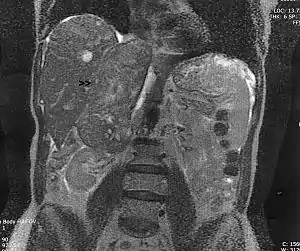

![]() Лейоміосаркома надниркових вен Лейоміосаркома надниркових вен | |